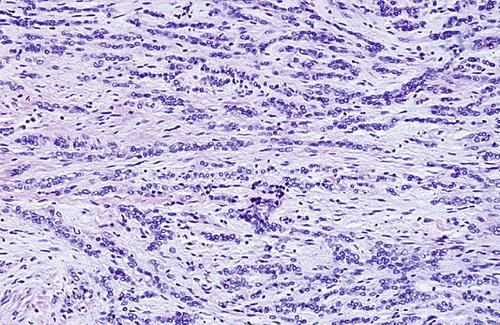

Chronic inflammatory infiltrate with associated acinar atrophy, ductal dilatation, and fibrosis.

chronic sclerosing sialadenitis